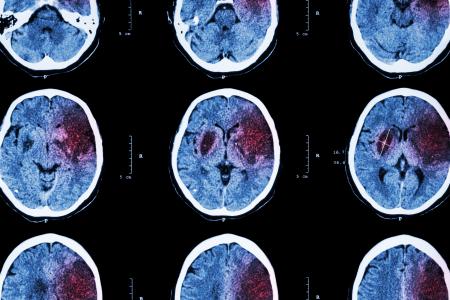

Cette recherche, menée par des neuroscientifiques de l’Université de Californie - San Francisco (UCSF) implique des facteurs connus comme l’inflammation et la santé cérébrovasculaire, et démontre, précisément les effets du stress dans la vingtaine sur les capacités cognitives à la quarantaine précisément, une neuro-inflammation plus élevée chez les jeunes adultes est liée à des performances moindres aux tests cognitifs à la quarantaine. Ces conclusions, présentées dans la revue Neurology, rappellent aussi l’impact de toutes les comorbidités de l’obésité sur la santé cérébrale et cognitive.

Cette association avait déjà été démontrée entre une inflammation plus élevée chez les personnes âgées et l’incidence de la démence, mais c’est la première recherche à relier l’inflammation au début de l’âge adulte à ce déclin cognitif à la quarantaine.